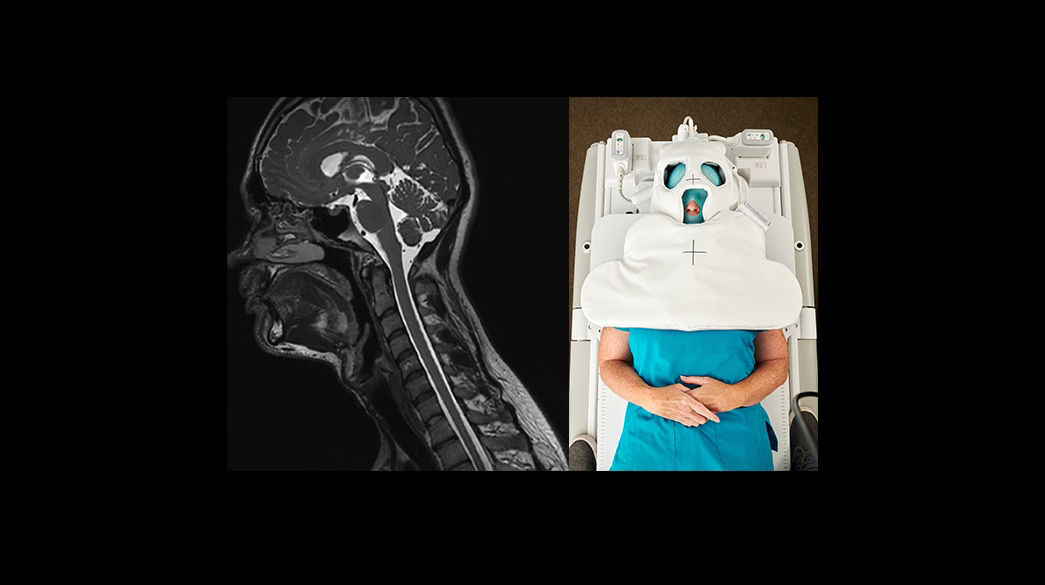

Personalized

Comfortable, acoustic reduced imaging, added to any patient